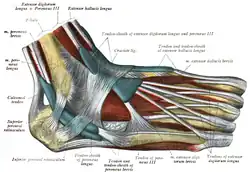

Mucous sheaths of tendons around right ankle, lateral aspect. (Tendon-sheath of fibularis longus labeled as peronaeus longus at bottom center.) | |

The muscle ends in a long tendon, which runs behind the lateral malleolus of the ankle in a groove that it shares with the tendon of the fibularis brevis; the groove is converted into a canal by the superior fibular retinaculum, and the tendons in it are contained in a common mucous sheath.[2]

The tendon then extends forward at an angle across the lateral side of the foot, below the fibular trochlea and the tendon of the fibularis brevis, and under cover of the inferior fibular retinaculum.[2] It crosses the lateral side of the cuboid and then runs underneath the cuboid in a groove that is converted into a canal by the long plantar ligament. The tendon then crosses the sole of the foot at an angle and inserts into the lateral side of the base of the first metatarsal and the lateral side of the medial cuneiform.[2] Occasionally, it also sends a slip to the base of the second metatarsal.[2]